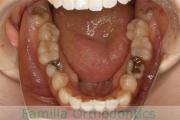

No.22V-449

- 主な症状:

- 上顎前突

- その他の症状:

- 叢生

- 年齢:

- 14歳

- 性別:

- 男性

- 抜歯部位

- 上:

- 44

- 下:

- 8448

- 主な使用装置:

- FEA

- 治療にかかった費用:

- 87万円

歯並びをきれいにしたいということで来院されました。上下左右から小臼歯を抜歯して、マルチブラケット法を行っています。2年弱、25回程度の通院が必要でした。

かなり強い叢生(でこぼこ、凹凸、ガタガタ)ですので、保定をしっかりしないと後戻りのリスクがあります。

- ≫治療後

-